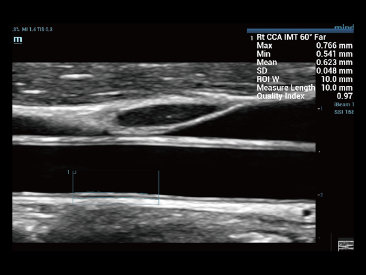

Die St?rken des Resona 7 sind bis ins kleinste Detail durchdacht. Seine erstklassige Bildqualit?t ist das Ergebnis einer erfolgreichen Fusion. Mindray und Zonare Medical Systems haben ihren Kernkompetenzen geb├╝ndelt, um ein Premiumsystem Wirklichkeit werden zu lassen. Dank der Vector Flow-Funktion k?nnen bei Gef??untersuchungen mehr als 400 Bilder pro Sekunde dargestellt werden. Somit entstehen ganz neue M?glichkeiten der Diagnose.

Dank der ZONE Sonography?-Technologie (ZST+) wird das B-Bild des Resona 7 ├╝ber die komplette Tiefe fokussiert, sodass keine Fokuspunkte mehr gesetzt werden m├╝ssen. Die Schall-Lauf-Geschwindigkeit (SSC) wird auf Knopfdruck individuell auf den Patienten angepasst, was die Darstellung von Organen, Grenzfl?chen und Gewebever?nderungen erheblich verbessert. Und dank der fortschrittlichen iFusion-Funktion k?nnen optional die Daten von Ultraschall-, MRT-und CT-Bildern synchronisiert werden.